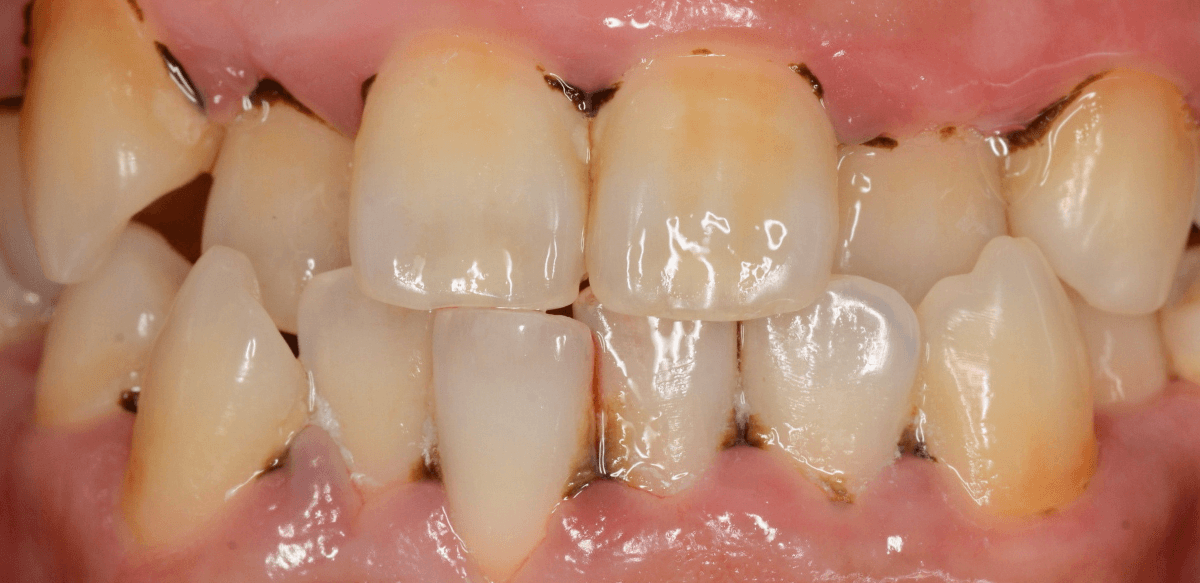

Case.4「歯の周りの黒い物を取って欲しい」という患者さん

今回は、「歯の周りの黒い物を取ってほしい」という訴えの患者さんのケースです。

着色かな、と思い口の中を拝見すると、歯の表面まで露出した縁下歯石でした。

当院は、(現在のところ)比較的若い患者さんが多いので、ここまでハッキリ縁下歯石が露出しているケースは珍しいです。

患者さんには、歯周病の基本的な説明とブラッシング指導をした後、まず下の歯の歯石除去から始めました。

ブラッシング指導・下の前歯の歯石除去直後の写真です。

これだけでも、かなり改善したかと思いますが、これだけの縁下歯石の量ですから、一回の歯石除去で全て取り切れるはずがありません。

根気よく、歯石除去を続ける必要があります。